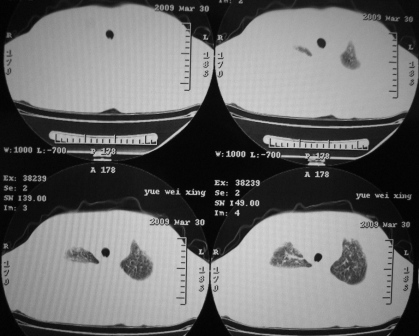

xx 男 43岁

右下叶支气管变窄闭塞,右下叶实变,双肺野弥漫性斑片状影,肺纹理增多增粗,纵隔多发淋巴结肿大,双侧胸水,考虑1双肺继发型结核,右下叶支气管内膜结核,双侧胸水2右下叶中央型肺癌伴右下叶实变,双肺转移,纵隔淋巴转移,双侧胸腔积液3淋巴瘤,请结合病史进一步检查。

病史呢?先考虑----右中央型肺癌继发下叶不张,双肺及纵隔淋巴转移,双侧胸腔积液,心包积液。

不排除---心脏病变所致

右肺下叶支气管中断闭塞,右下肺见不规块影,并胸腔积液,考虑肺中央型肺癌继发下叶不张,\\双侧胸腔积液,心包积液。

考虑右中央型肺癌并下叶不张,双侧胸腔积液,心包积液

右侧中央型肺癌伴右肺下叶不张,双肺及纵隔淋巴转移,双侧胸腔积液,心包积液。